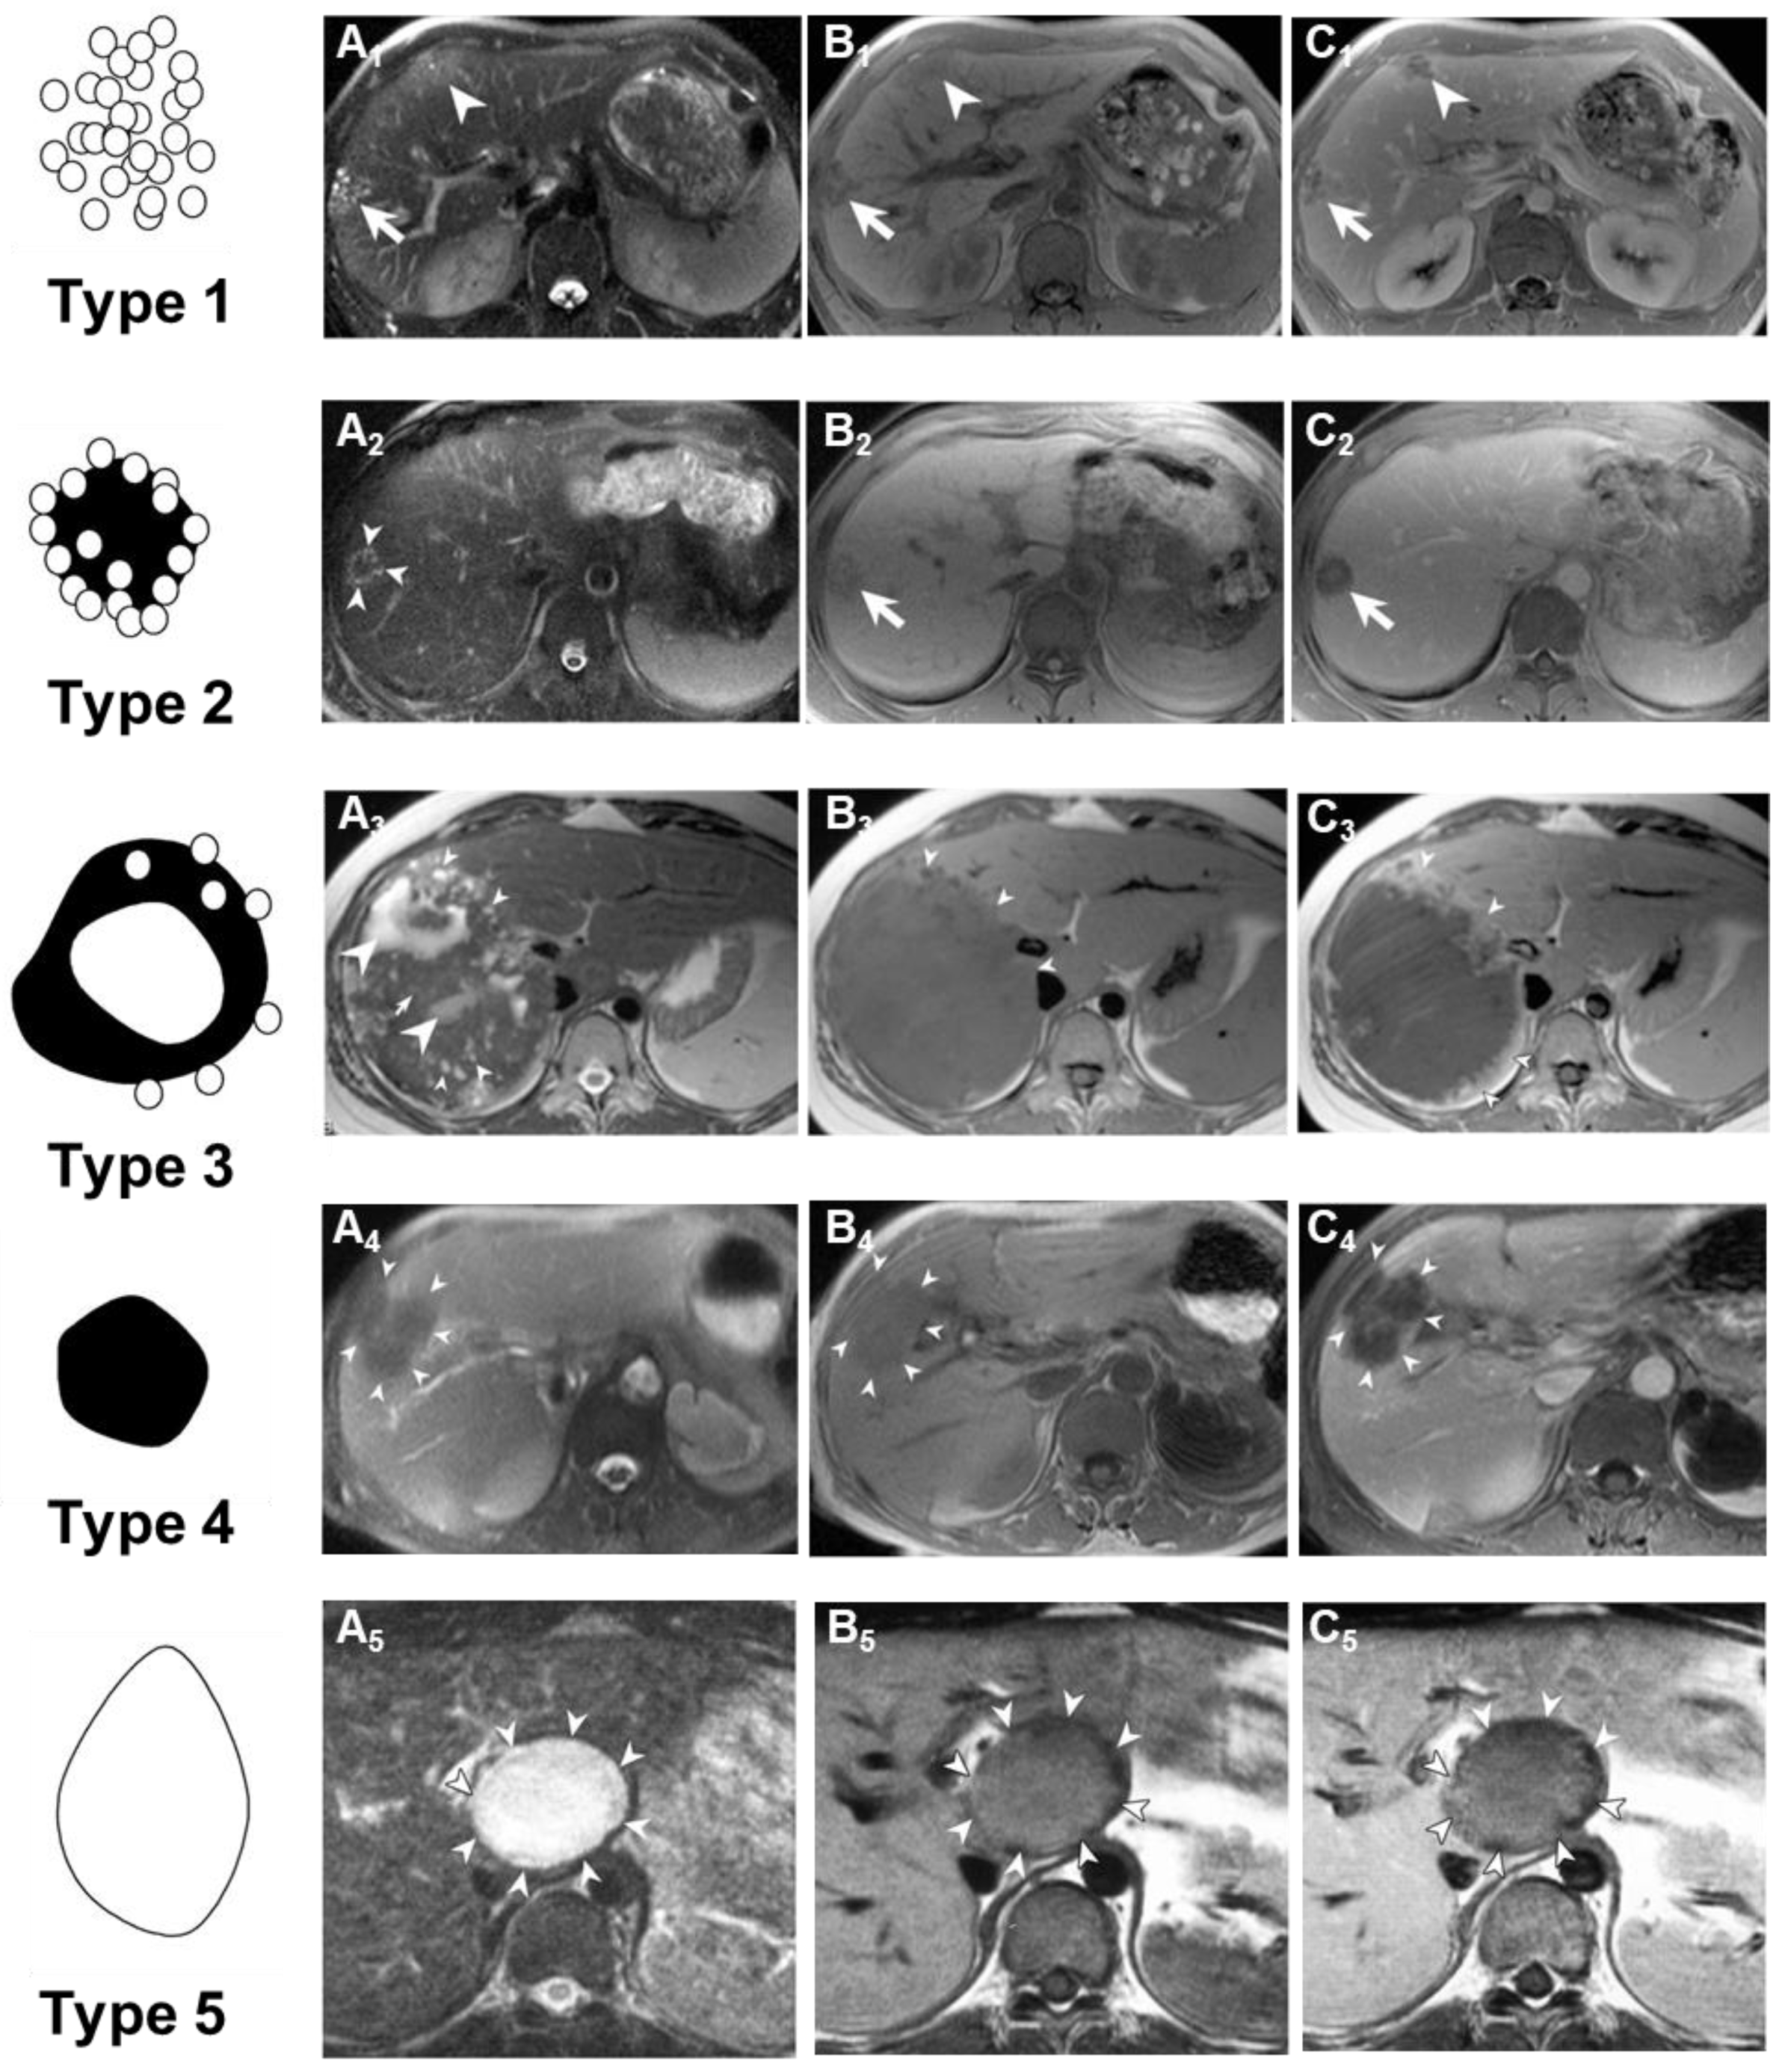

In 2003, Kodama and colleagues classified the MRI imaging results of patients with AE (Figure 7) [133]. They classified AE into five types based on its imaging manifestations on MRI: Type 1 consists of multiple small round cysts without a solid component; Type 2 features multiple small round cysts with a solid component; Type 3 is characterized by a solid component surrounding large and/or irregular cysts with multiple small round cysts; Type 4 comprises a solid component without cysts; and Type 5 is a large cyst without a solid component. The reliability of Kodama’s classification is excellent and has received widespread recognition, allowing for the identification of five types of liver lesions based on morphological features on T2-weighted MRI sequences. Brumpt et al. further refined the Kodama classification by subdividing Type 3 into IIIa with microcysts and IIIb without, based on the crucial role of microcysts in therapeutic decision-making for AE lesions [136]. T2-weighted MRI imaging exhibits better imaging performance in the early diagnosis of AE, compared to CT or US. In a 74-year-old male patient, seven years after resection of rectal cancer, CT scans and ultrasound images revealed two small, uniform low-density and hypoechoic lesions in the liver, respectively. These lesions were later histologically confirmed as early but active AE. Abdominal MRI, on T2-weighted images, demonstrated two isointense tumor lesions with small areas of high-signal intensity at their centers. The MRI findings seemed to accurately reflect both the macroscopic and microscopic manifestations of early AE, with each liver lesion containing an active cyst at its center [137].

The assessment of the metacestode activity status using 18-fluoro-deoxyglucose positron emission tomography combined with computed tomography (PET/CT) is widely accepted and recognized. Azizi et al. [138] correlated the presence of AE liver lesions defined by Kodama et al. on MRI with metabolic activity visualized on PET/CT and found that the presence of microcysts in AE liver lesions detected by MRI is associated with metabolically active disease. Their study revealed that all Type 1 and the majority of Type 2 (90.9%) and Type 3 (87.5%) lesions exhibited increased perilesional FDG uptake on PET/CT images. In fact, all three types are composed of multiple small cysts, which directly reflect the infracentimetric parasitic vesicles. These small cysts cluster around the periphery of the lesion in a “bunch of grapes” or a “honeycomb-like” patterns, which are considered to represent the early stages of the disease. In fact, the correlation between the microvesicle images on MRI and positive PET/CT is likely explained by more numerous and metabolically active immune cells within the lesion areas where active vesicles are present [139]. A study has shown that imaging features based on T2-weighted imaging (T2WI) and machine learning models can be used to assess the biological activity of HAE lesions, which is conducive to the selection and monitoring of clinical treatment methods [140]. Susceptibility-weighted imaging (SWI) is an MRI technique that may assist in identifying calcified regions and has recently been proven to detect liver calcification, potentially reducing the need for CT imaging in assessing echinococcosis [141]. Intravoxel incoherent motion diffusion-weighted magnetic resonance imaging (IVIM DW MRI) was compared with T1 mapping for the characterization of HAE, revealing that IVIM-derived parameters, especially the perfusion fraction (f), provided better differentiation of solid HAE components from background liver parenchyma than T1 relaxation times [142].